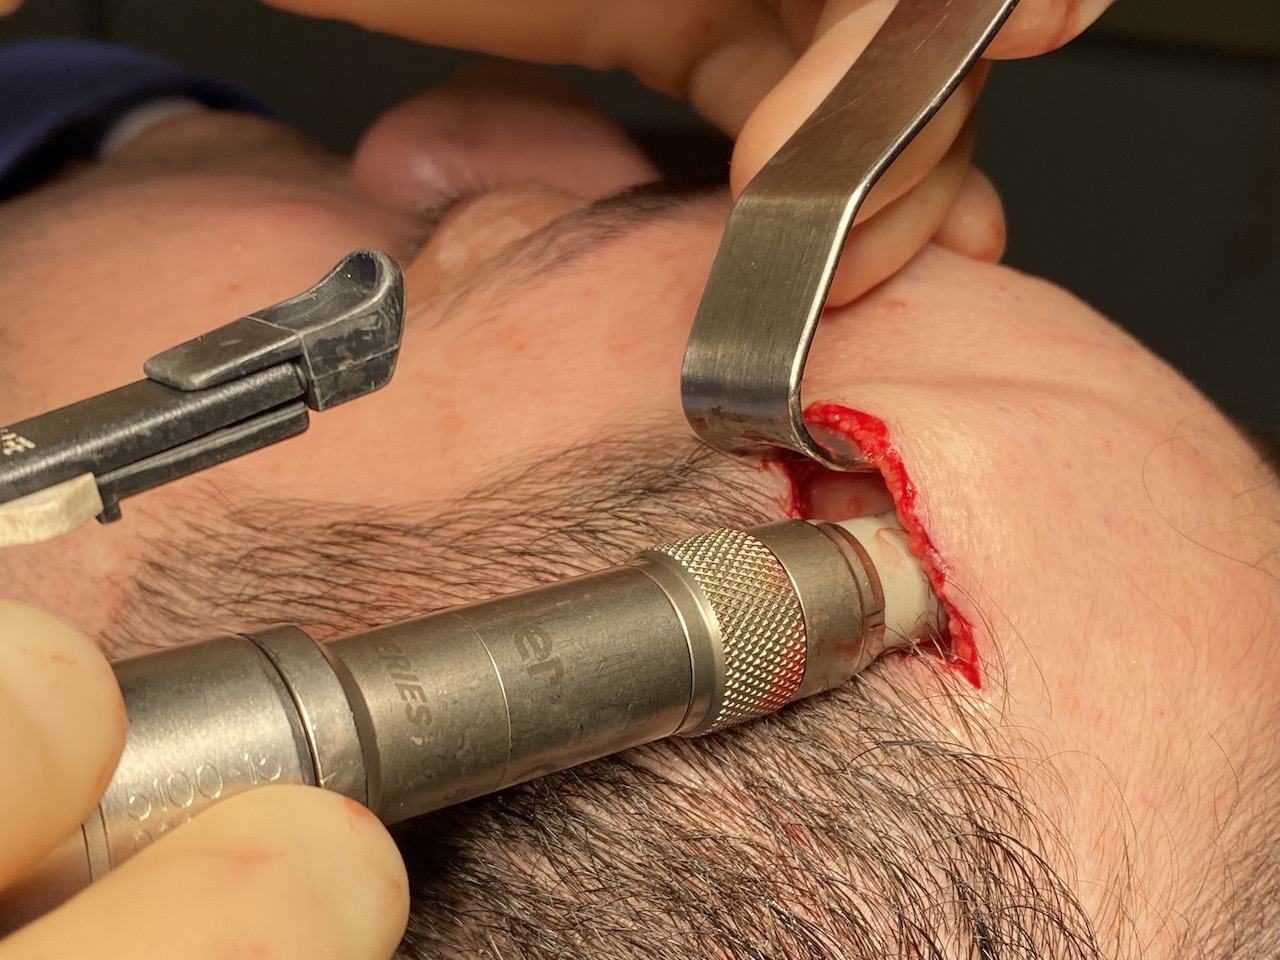

Desire for reduction of prominent occipital knob deformity.

Intraoperative result from occipital knob skull reduction through a direct small scalp incision.